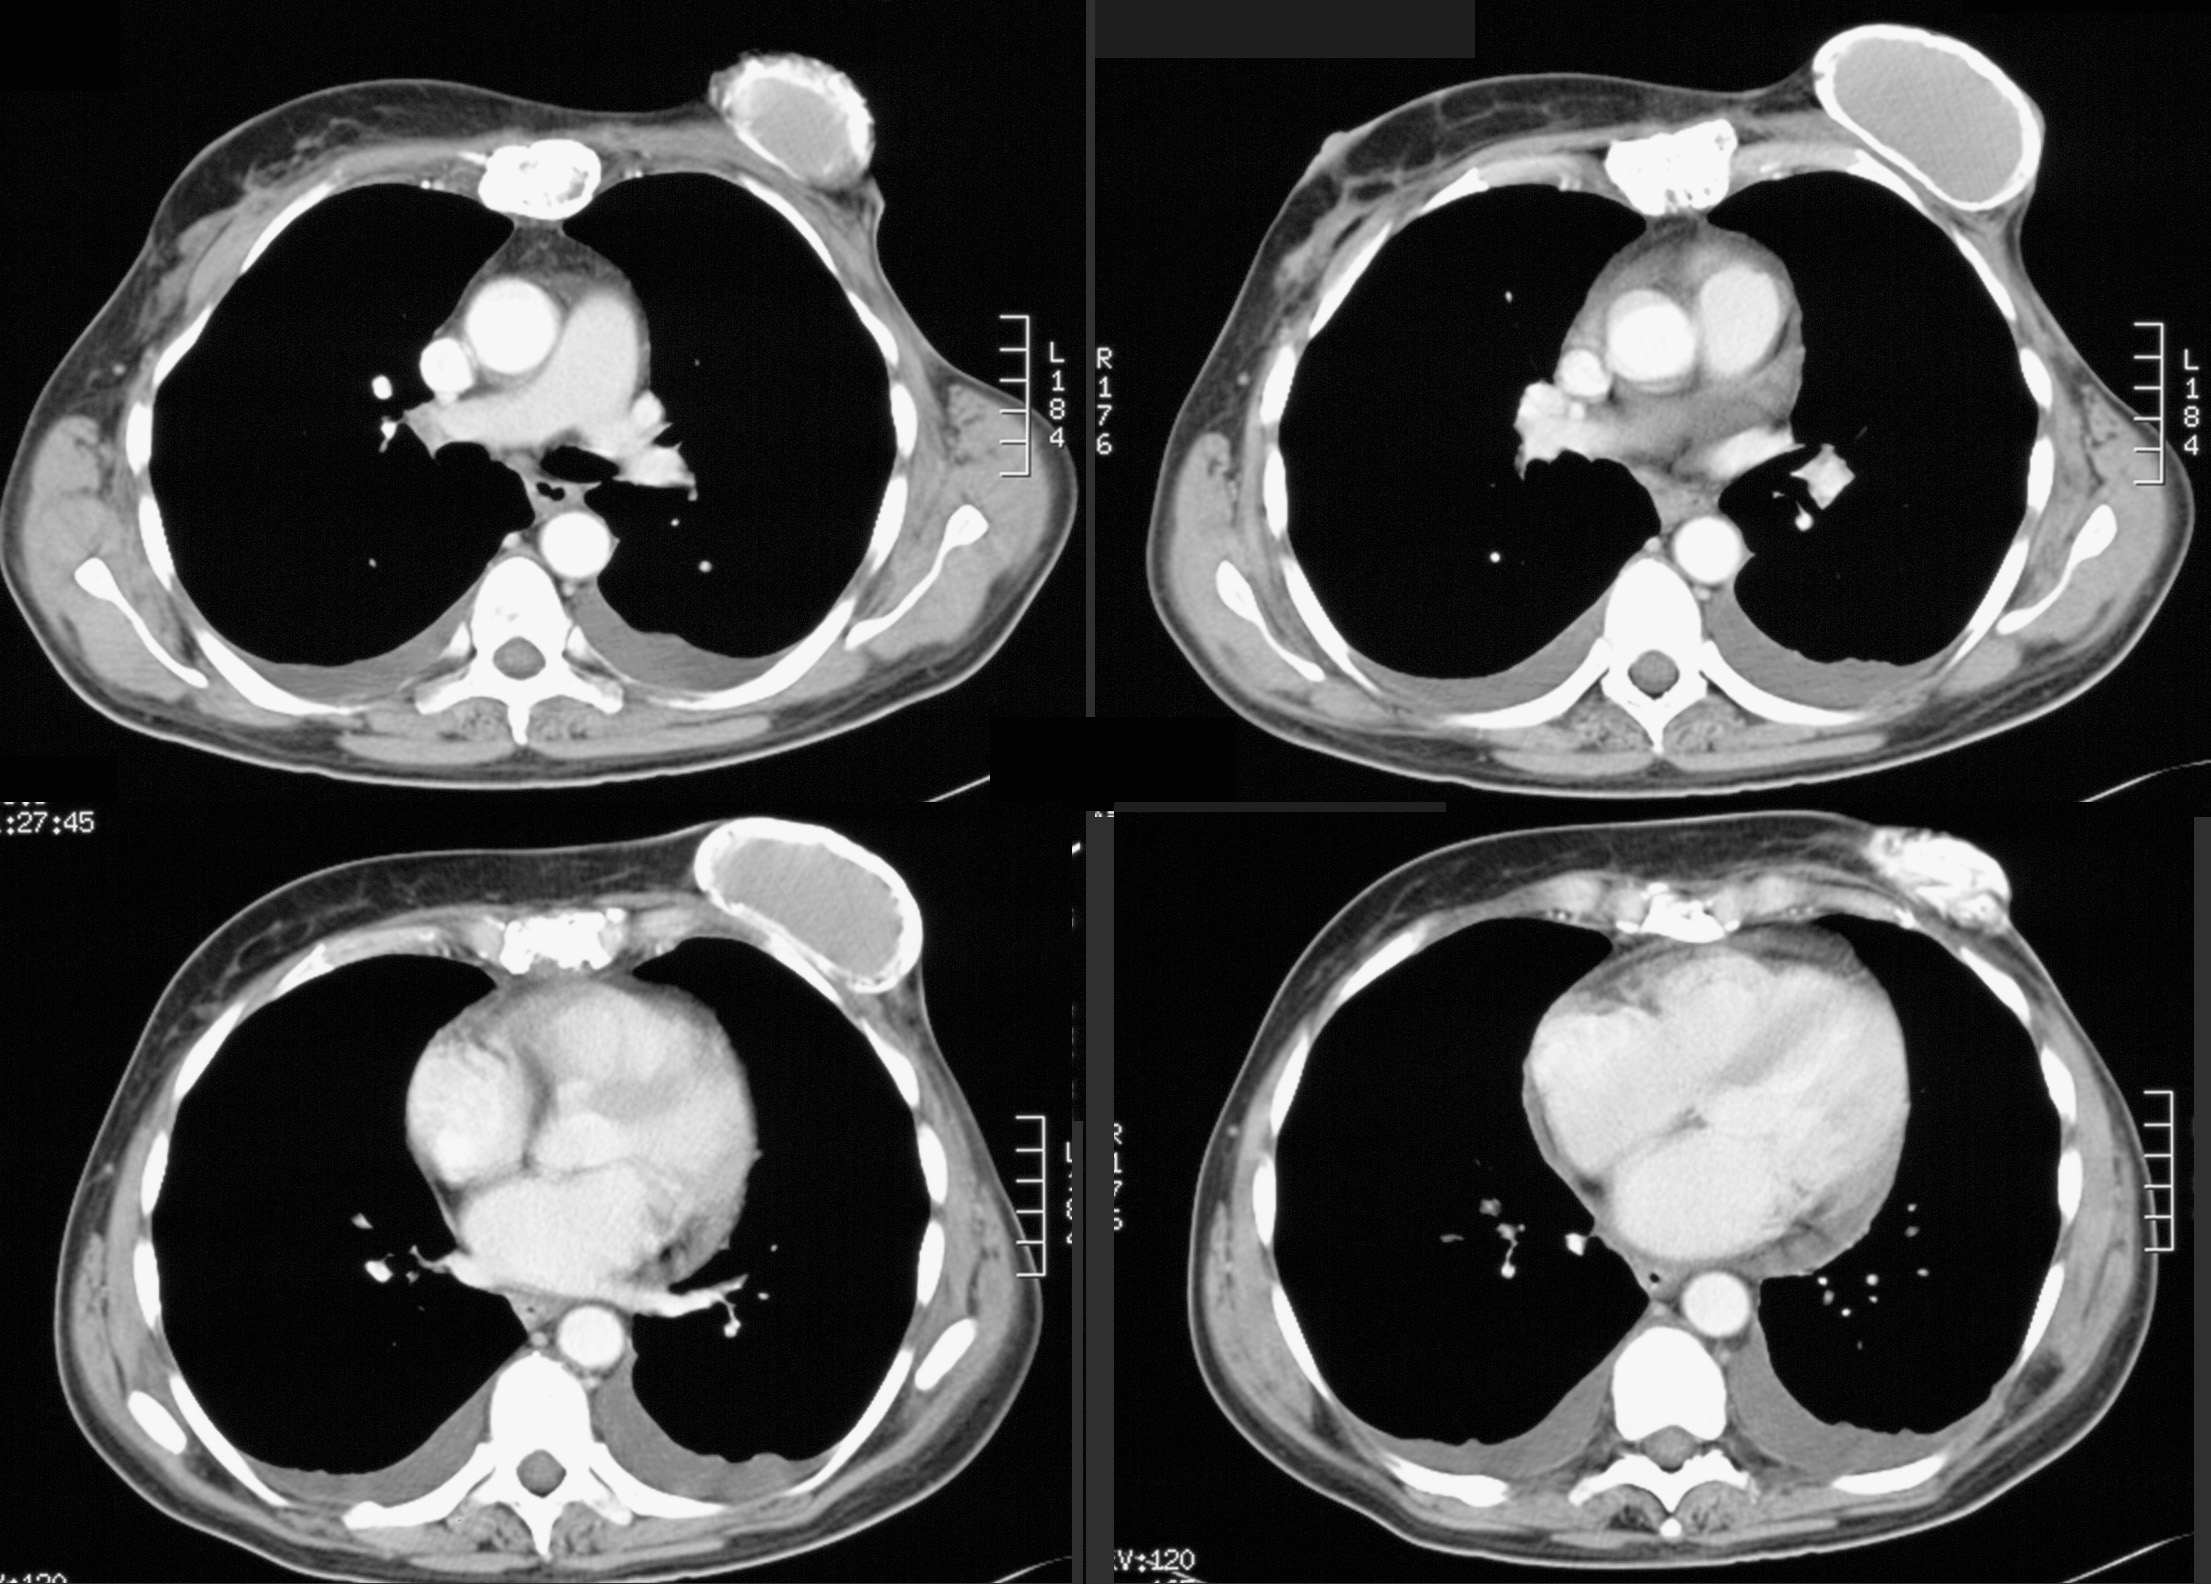

◂Breast Anatomy